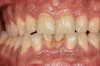

Intrinsic staining is deeper staining embedded within the dentin of the tooth.3,7 Causative factors of intrinsic staining include dental caries, enamel defects such as enamel microcracks, restorations, genetics, aging, trauma, medications, environment, or systemic conditions, as well as excessive fluoride ingestion, severe jaundice in infancy, and porphyria3,7 (Figure 1).

Fig 1. Intrinsic staining.

Figure 1